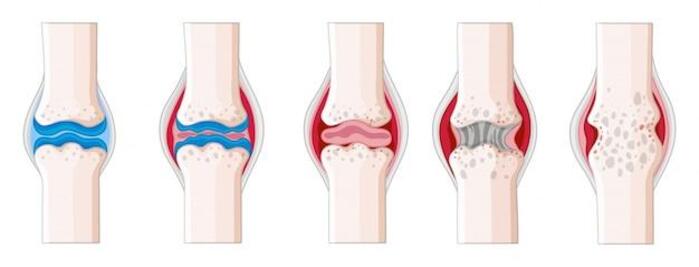

При ревматоидном артрите усиливается течение симметричных артритов мелких суставов (обычно стоп или кистей), а также, в более редких случаях, крупных суставов. Симметричные артриты могут выражаться в припухлости, покраснении, болезненных ощущениях, повышении температуры. Поражения часто носят симметричных характер, возможно появление болей покоя. Все это переходит в повышенную утомляемость, недомогание. Утром возможна долгая скованность движений (обычно около часа). Ревматоидный артрит поражает также внутренние органы, развивается плеврит. У четверти пациенток могут возникать ревматоидные узелки под кожей на месте сгибов суставов. Треть пациенток могут ощущать сухость слизистой во рту и глазах, испытывать воспаление сердечной сумки. Соответственно, повышается риск развития сердечно-сосудистых заболеваний. У женщин с проблемами лишнего веса или вредными привычками симптомы обычно сильнее, а с возрастом течение заболевание происходит активнее.1